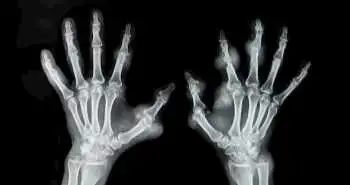

Применение ритуксимаба в сочетании с метотрексатом для лечения ревматоидного артрита является безопасным и превосходит по эффективности монотерапию метотрексатом.

По результатам систематического обзора и метаанализа рандомизированных контролируемых исследований (РКИ) по сравнению применения ритуксимаба в сочетании с метотрексатом и монотерапии метотрексатом выявлено, что оценка по критериям ACR20, ACR50 и ACR70 у пациентов с ревматоидным артритом была статистически значимо выше на фоне комбинированной терапии, чем на фоне монотерапии метотрексатом. Отсутствовали различия общей частоты развития осложнений и инфекционных заболеваний. Отбор РКИ для метаанализа проводили путем поиска по электронным базам данных PubMed, Google, Кокрейновской библиотеки и китайской базе данных Wanfang.

Конечные точки исследования включали оценку по критериям ACR20, ACR50, ACR70, общую частоту развития осложнений и инфекционных заболеваний. 5 отобранных РКИ включали 3299 пациентов из группы лечения ритуксимабом в сочетании с метотрексатом и 1512 пациентов из группы монотерапии метотрексатом. Результаты метаанализа свидетельствуют об эффективности и безопасности комбинированной терапии для лечения пациентов с ревматоидным артритом. Тем не менее, необходимо проведение дальнейших исследований по оценке долгосрочной безопасности применения данной комбинации препаратов.